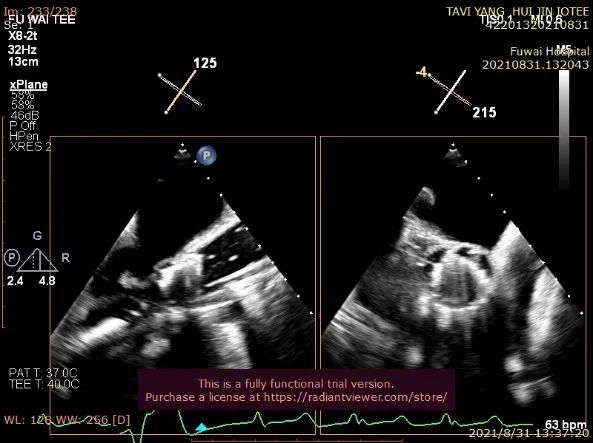

TA-TAVR在全麻和气管插管下进行。经右侧股静脉置入临时起搏器,经右侧股动脉在患者主动脉无冠窦内放置1根6F猪尾导管进行协助定位(图1)。

图1. TEE和放射线显示猪尾导管、临时起搏导线、导丝

透视下定位后第五肋间小切口进胸,打开心包,选择心尖裸区缝制六边形荷包。心尖穿刺后将泥鳅导丝过主动脉瓣经升主动脉、主动脉弓到达降主动脉膈肌水平,通过TEE确认细导丝没有与二尖瓣腱索缠绕(图2)。

图2. TEE和放射线显示输送器进入升主动脉根部、瓣环平面以上水平